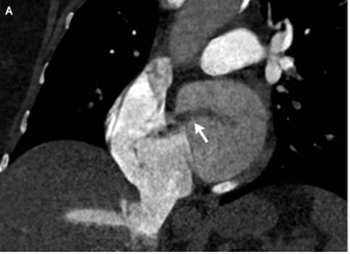

造影CTが施行され、肺動脈における肺塞栓、右心拡張、これまで知られていなかった卵円孔開存(PFO:patent foramen ovale)が認められた。